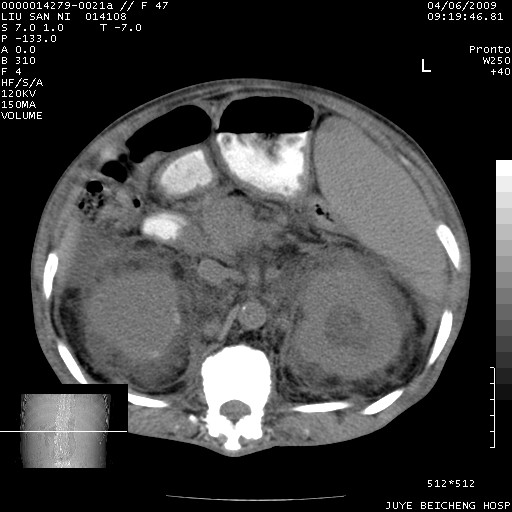

以下是引用前行在2009-4-7 10:31:00的发言:[br]肝脾肿大;双肾增大,双肾盂少量积水可能,肾膜膜增厚,肾周间隙增宽,并见桥间隔,提示结缔组系统疾病、系统性红瘢狼疮肾可能性大。继发右侧胸腔、心包、腹腔积液。

以下是引用深泽交通医院在2009-4-7 11:21:00的发言:[br]双侧肾周密度增高,见条索影,右肾实质见点片状低密度区,考虑弥漫肾炎【自身免疫性?】;;肾性水肿征